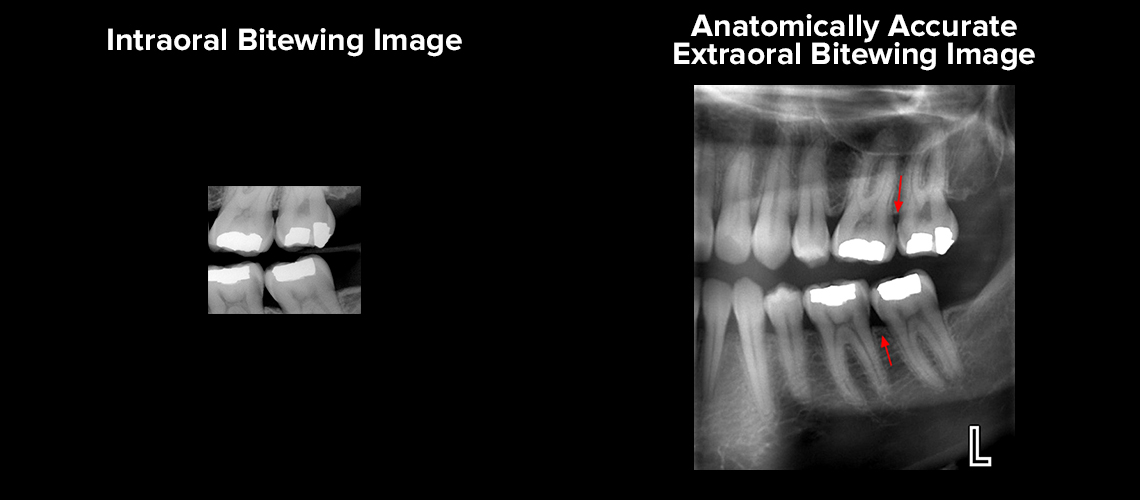

Extraoral images are acquired when the image receptor is positioned outside of the patients mouth. Describe the purposes and uses of extraoral imaging. Extraoral radiographs do not show the details as well as intraoral films.

Discuss the advantages of 3D imaging. Define the key terms associated with extraoral imaging Describe the purpose and uses of extraoral imaging Describe the head position the receptor placement and beam alignment for the various extraoral images. Extraoral radiographs do not show the details as well as intraoral films do.

Identify and describe the equipment used in extraoral imaging. After a thorough clinical and radiographic examination a conclusive diagnosis was determined and surgical. Extraoral radiographs are very useful for evaluating large areas of the skull and jaws but are not adequate for detection of subtle changes such as the early stages of dental caries or periodontal disease.

More recent innovations include the use of digital CT scans and 3D imaging in the dental office similar to CT scans done in hospitals and medical imaging centers. Describe the equipment used in extraoral imaging. Extraoral radiographs are useful in evaluating large areas of the skull and jaws but are not adequate for detection of subtle changes such as the early stages of dental caries or periodontal disease.